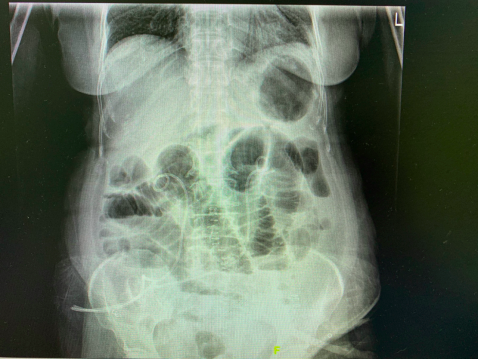

05.放射学检查证实(典型立位腹部平片见下图)

小肠低位不完全性肠梗阻. 可见中下腹小肠肠腔扩张,积气,多个长短不一气液平面。肠壁无明显增厚。胃泡可见,结肠和直肠内仍可见少许气体。双膈下未见气体影。

几乎所有早期术后机械性肠梗阻患者刚开始肠道功能都有所恢复并能经口摄食,此后才发生恶心、呕吐、腹痛和腹部膨隆,而肠麻痹患者通常不会出现肠道功能恢复。若结合平片仍不能鉴别肠麻痹与机械性梗阻,可行腹部 CT。